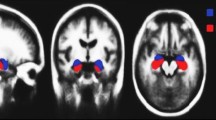

Finally, Region of Interest Segmentation: the preprocessed DTI data is utilized for segmentation of the hippocampus, as shown in Figs. 2 and 3. FSL’s FIRST toolset, employing a probabilistic atlas-based approach, enables accurate and reliable extraction of this key region. To form the ROI later to be analyzed and diffusion parameter calculated for further investigating to check the potential involvement in AD pathology.